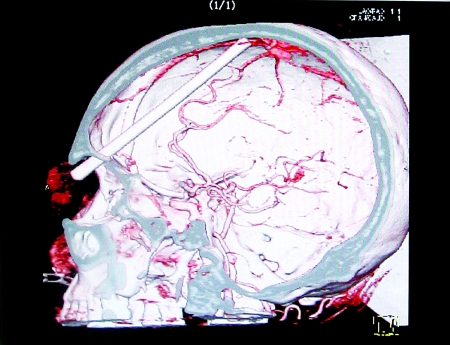

CT顯示頭顱里20厘米長的筷子(圖示處)。

中國日報網(wǎng)消息:老人與人發(fā)生肢體沖突,約20厘米的一截筷子從眼眶插進他頭顱,卻只在眼皮上留下一個小洞,也不見出血;親人沒發(fā)現(xiàn)異樣,1個小時后才送他去醫(yī)院。昨日,老人被緊急轉(zhuǎn)往西南醫(yī)院接受手術(shù),生死未卜。

取筷子可能大出血

當晚,鄭有成被送到了西南醫(yī)院腦外科ICU。西南醫(yī)院神經(jīng)外科教授孟輝告訴記者,筷子是從鄭有成的左眼眼眶直接插入顱內(nèi)的,因插入速度很快,傷者感覺不到劇烈疼痛,流血也很少。目前,不能直接拔出筷子,只能通過開顱手術(shù)取筷子。

孟輝說,筷子插入的是鄭有成左側(cè)大腦的功能區(qū),正好是支配人說話的地方,手術(shù)稍有差錯會造成失語或者癱瘓,筷子拔出時顱內(nèi)壓力釋放,還可能造成顱內(nèi)大出血,有生命危險。